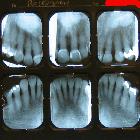

Examples of

dental radiography